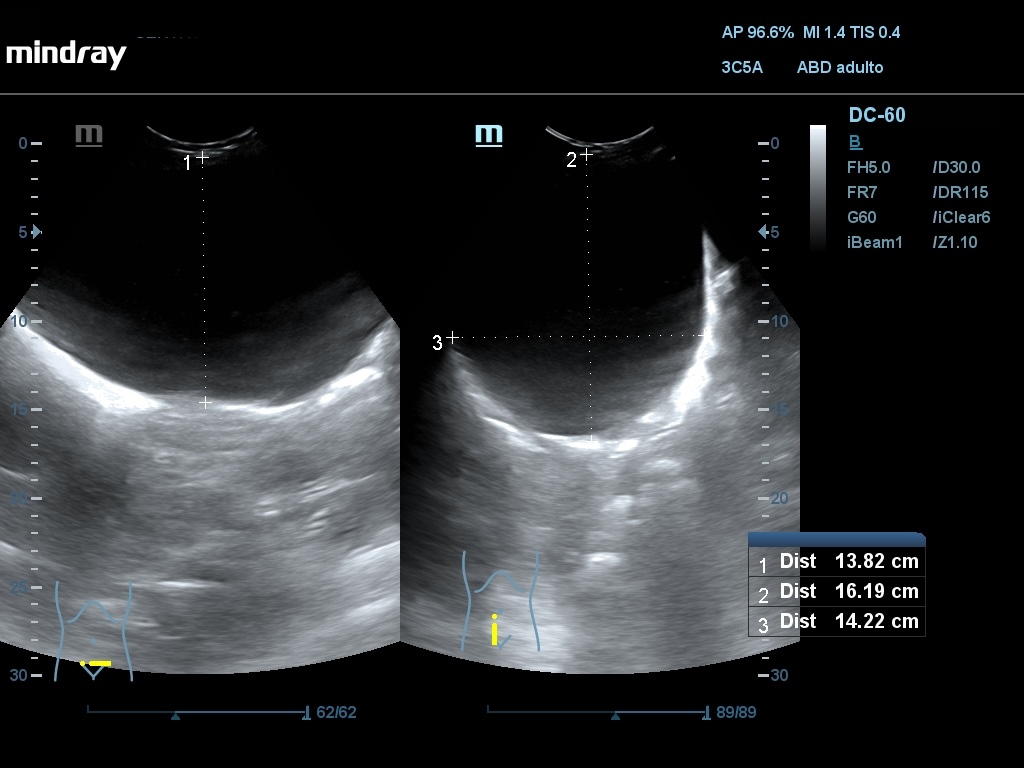

Ecografía abdominal: Se observan varios quistes simples a nivel hepático, siendo el mayor de 52,4 mm, en ambos riñones siendo el mayor de 77 x 83 mm en RD y de 80 x 64 mm en RI. En hipogastrio se observa imagen redondeada, anecogénica, con sombra posterior, de borde liso y fino, no tabicada, de aprox. 161 x 142 mm y otra de características similares de 74 x 54 mm.

Se describe imagen de 22 cm con probable localización anexial izq. El crecimiento del quiste ha condicionado un desplazamiento del mismo hacia cavidad abdominal derecha, desplazando lateralmente las asas del intestino y colon.